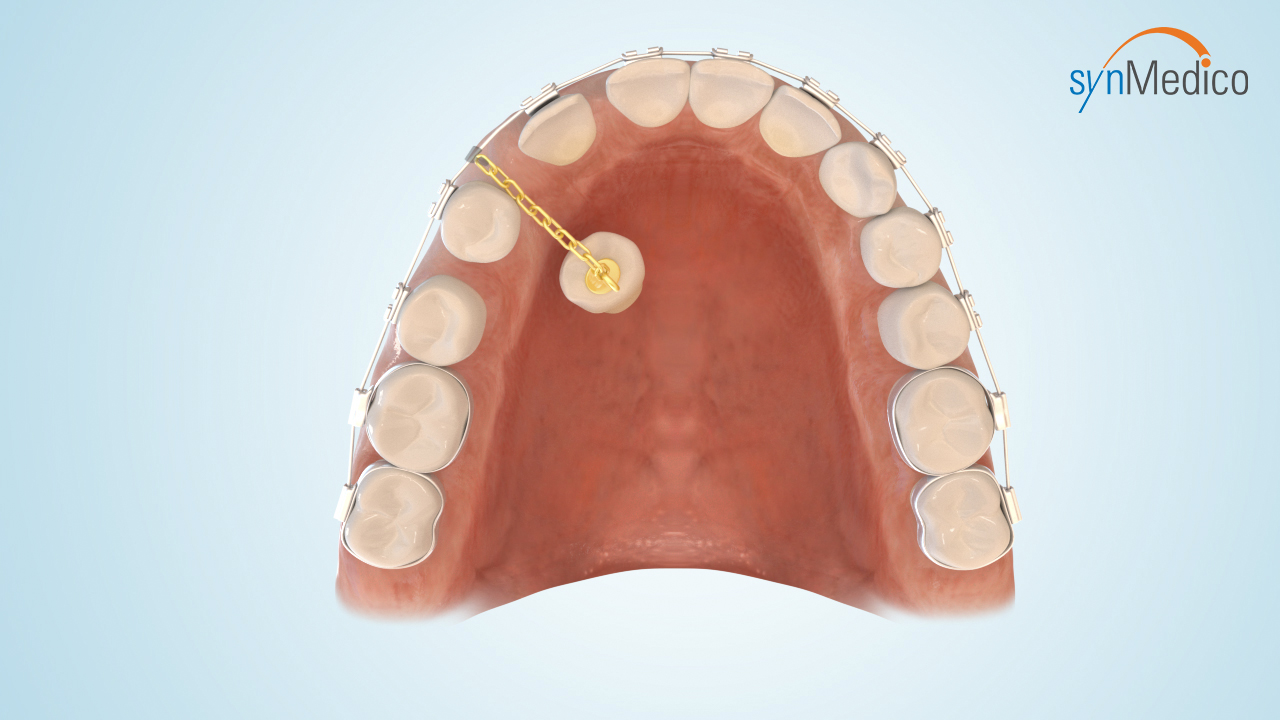

Freilegung von Zähnen

Gelegentlich verbleiben Zähne in der Wachstumsphase im Kiefer, da eine Blockade durch Nachbarzähne den Durchtritt verhindert. Durch eine kombinierte Behandlung mit den Techniken der Kieferorthopäde und der Kieferchirurgie können solche Zähne in die Zahnreihe eingestellt werden.